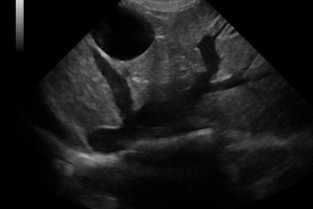

Imagerie Médicale

Ces travaux pratiques, réalisés par manipulation sur les chiens de compagnie appartenant aux participants, s’adressent à des vétérinaires canins désirant se former à l’échographie et disposant d’un échographe dans leur pratique quotidienne, ou souhaitant en acquérir un rapidement.

• d’identifier tous les organes lors d‘une échographie abdominale

• Il sera également capable de reconnaitre un aspect normal échographique pour chaque organe